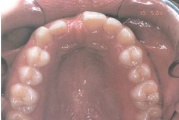

Ühepoolse lõhega lapse hambumus (puudub hammas lõhe piirkonnas).

Kaasasündinud hammaste puudumine

Sagedamini puuduvad hambad: teised premolaarid, ülemised lateraalsed intsisiivid, alumised tsentraalsed intsisiivid.